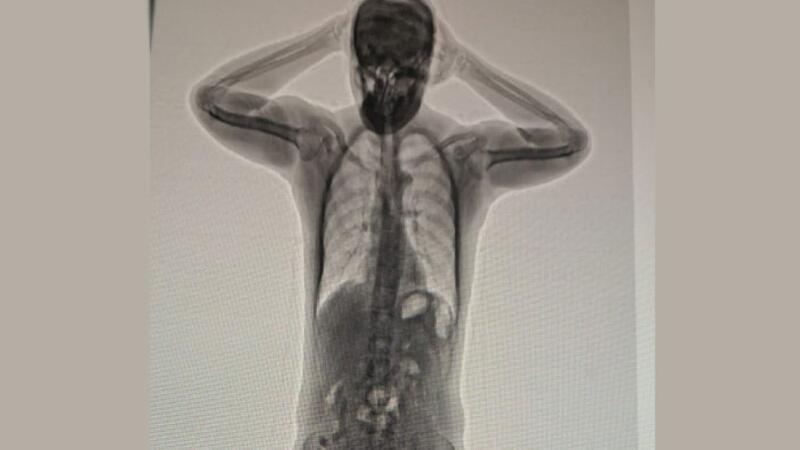

An expat was arrested for attempting to smuggle 50 capsules of heroin inside his body, the Royal Oman Police has announced.

The expat, who is of “Asian” nationality was arrested at the Muscat International Airport, officials revealed.

According to the Royal Oman Police, “An Asian national was arrested on charges of possessing narcotic drugs for the purpose of trafficking. More than 50 capsules of heroin were found inside him.”